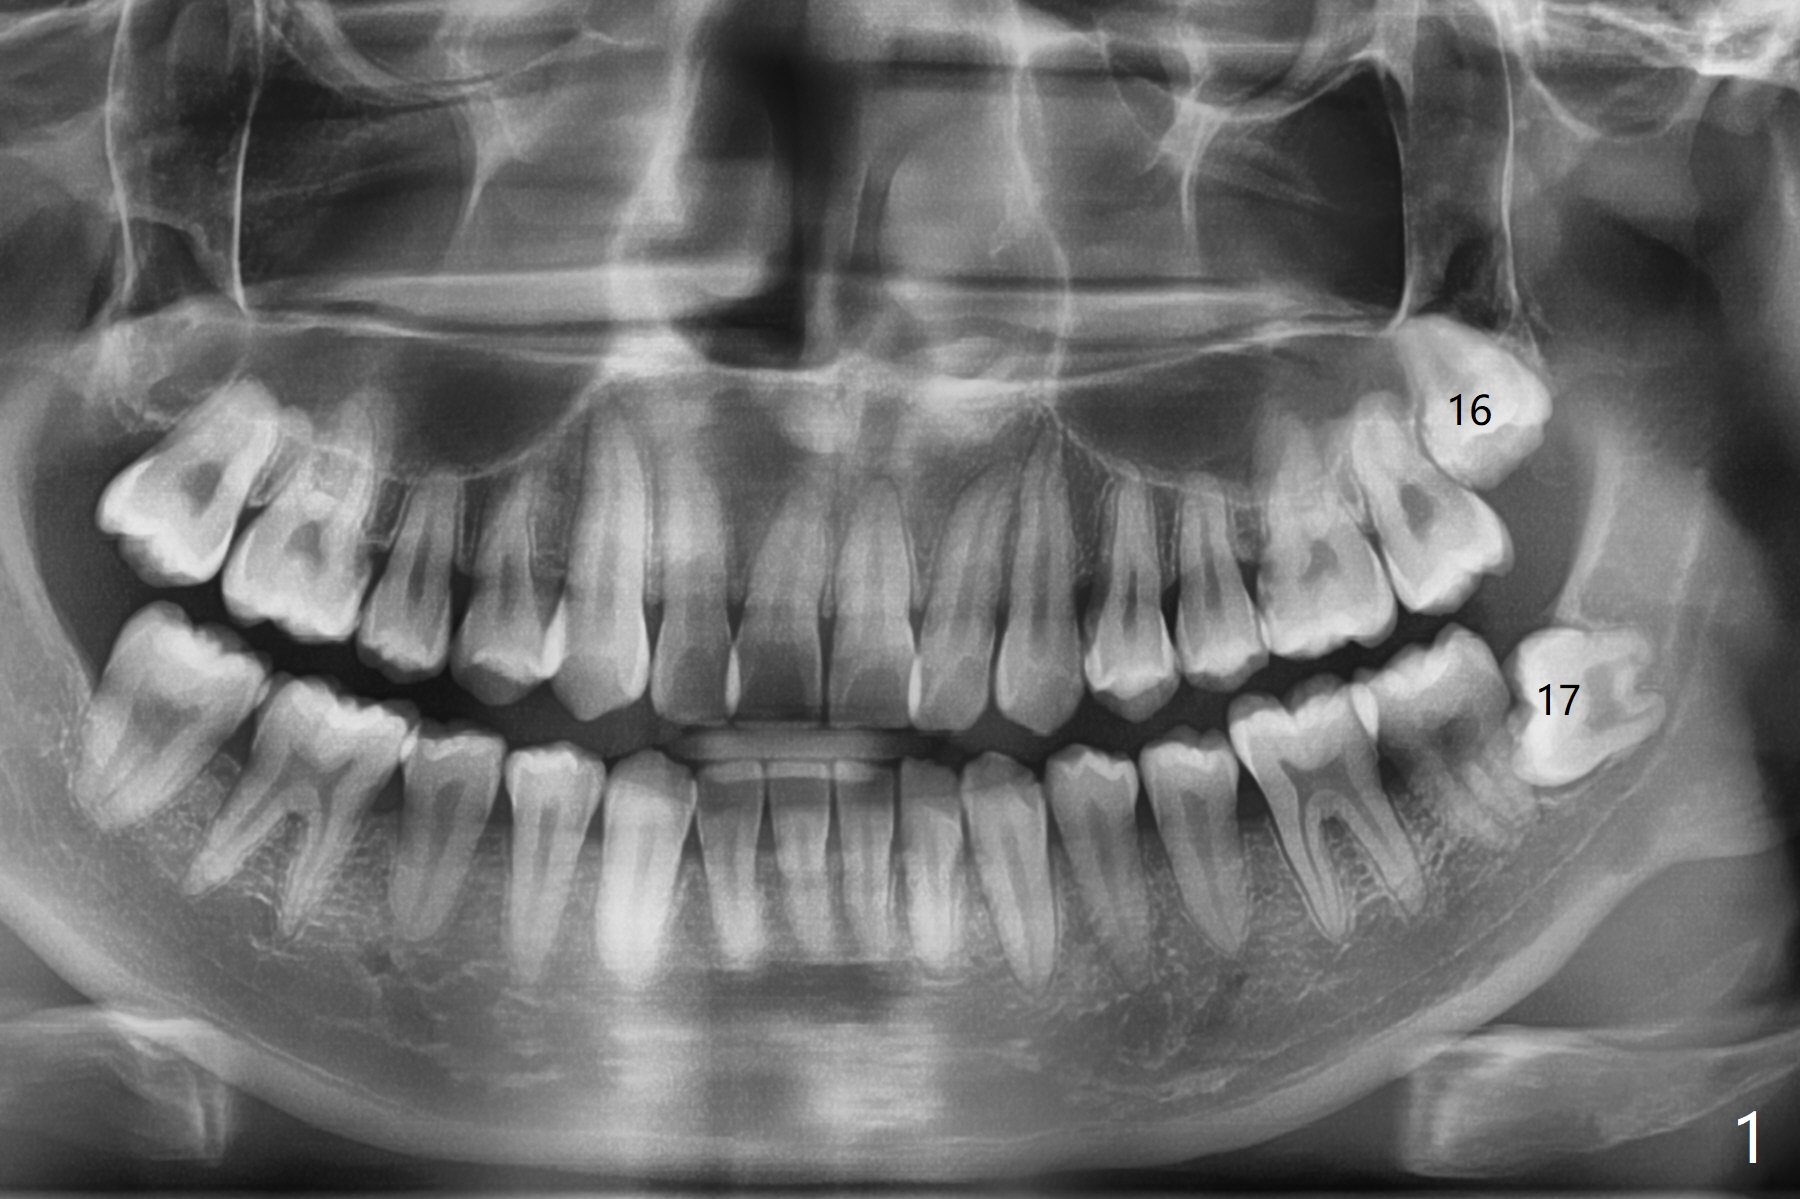

A 22-year-old man agrees with extraction of #16 and 17 with bone graft in the latter socket (Fig.1). Because of horizontal impaction, the mesial root tip (Fig.1' *) overlaps with the Inferior Alveolar Canal. 5x5 cm CT will be taken with special bite block to show the ramus as posterior as possible (internal and external oblique ridges). Since the crown of the 3rd molar seems to be buccal to the distal portion of the 2nd molar, the anterior oblique incision should be placed as mesial as possible (Fig.2 red line). After extraction, collagen plug (Fig.3 large white area) will be inserted into the root sockets, while sticky bone (circles) in the coronal socket. The latter will be covered by 2 pieces of PRF membrane, followed by compressed Osteogen Plug (small white area, tp be visible in the postop panoramic 2 bitewings).